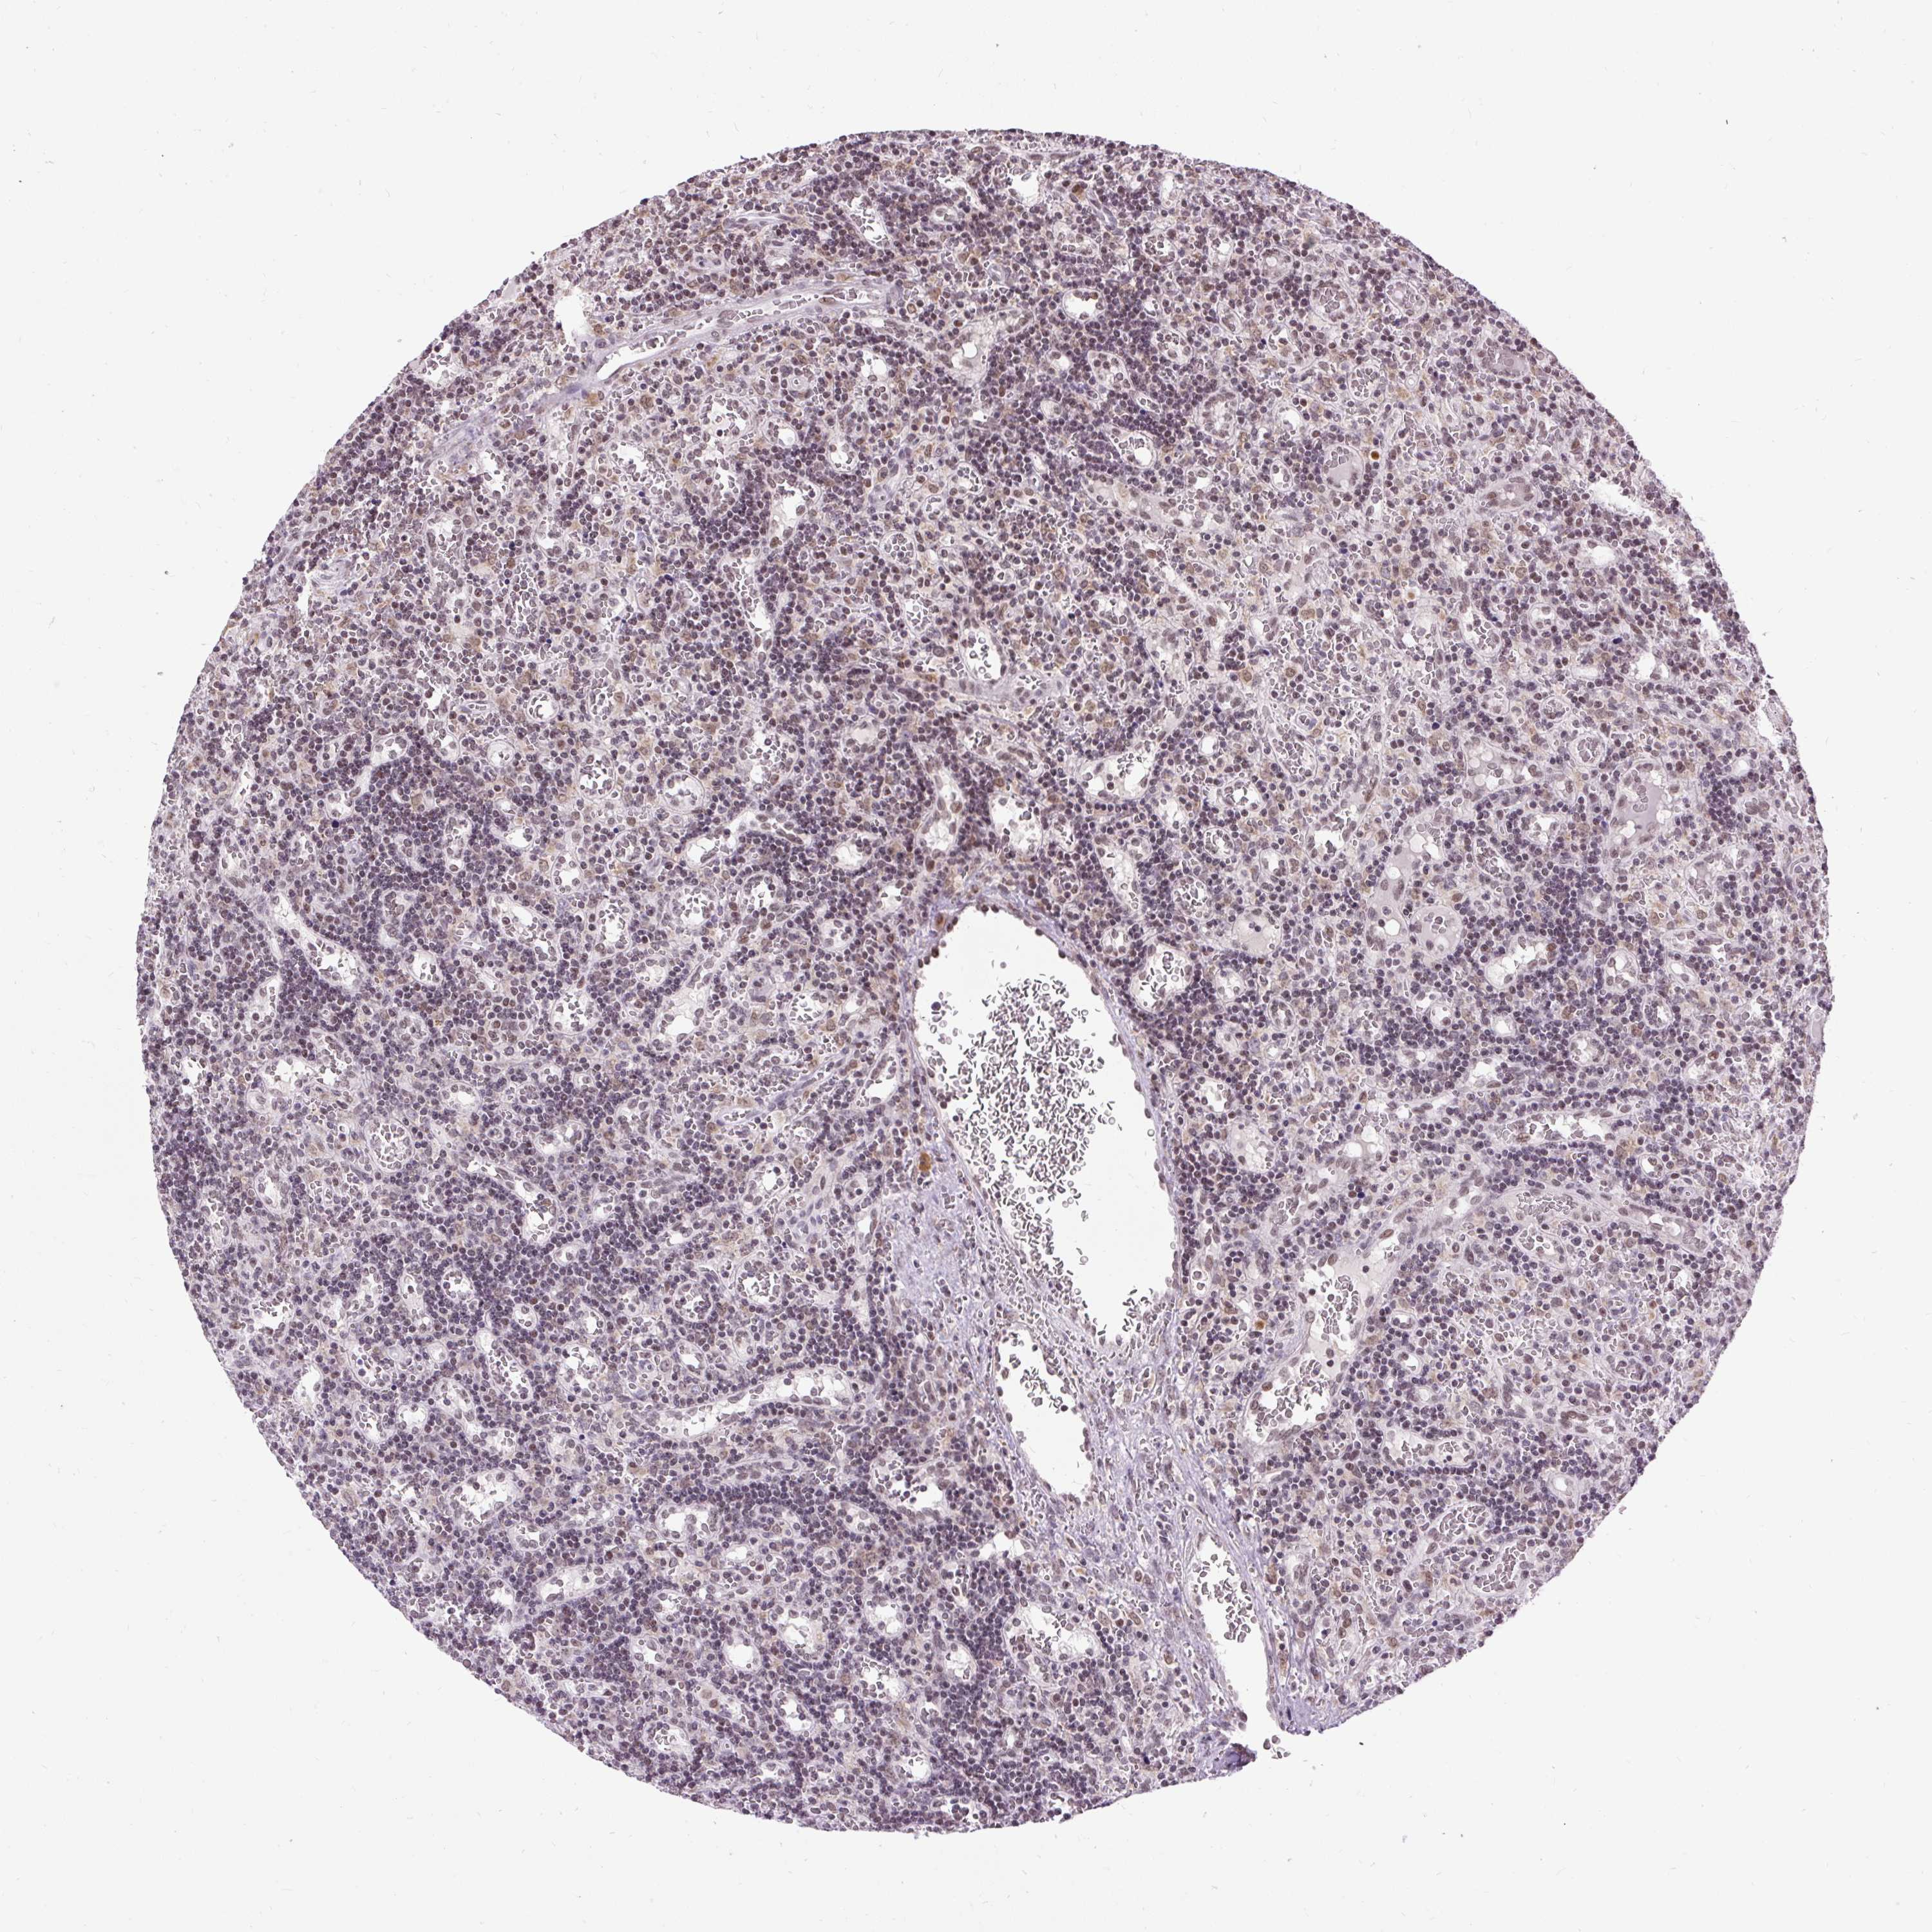

LYMPHOMA - Protein expressioni

A mouse-over function shows sample information and annotation data. Click on an image to view it in a full screen mode. Samples can be filtered based on level of antibody staining by selecting one or several of the following categories: high, medium, low and not detected. The assay and annotation is described here.

Each image is clickable and will lead to virtual microscopy that enables deeper exploration of all samples and also displays staining intensity scores, fraction scores and subcellular localization as well as patient and tissue information for each sample.

Antibody HPA055779

Staining

High

Medium

Low

Not detected

Intensity

Strong

Moderate

Weak

Negative

Quantity

>75%

75%-25%

<25%

None

Location

Nuclear

Cytoplasmic/membranous

Cytoplasmic/membranous,nuclear

Malignant lymphoma, non-Hodgkin's type, Low grade